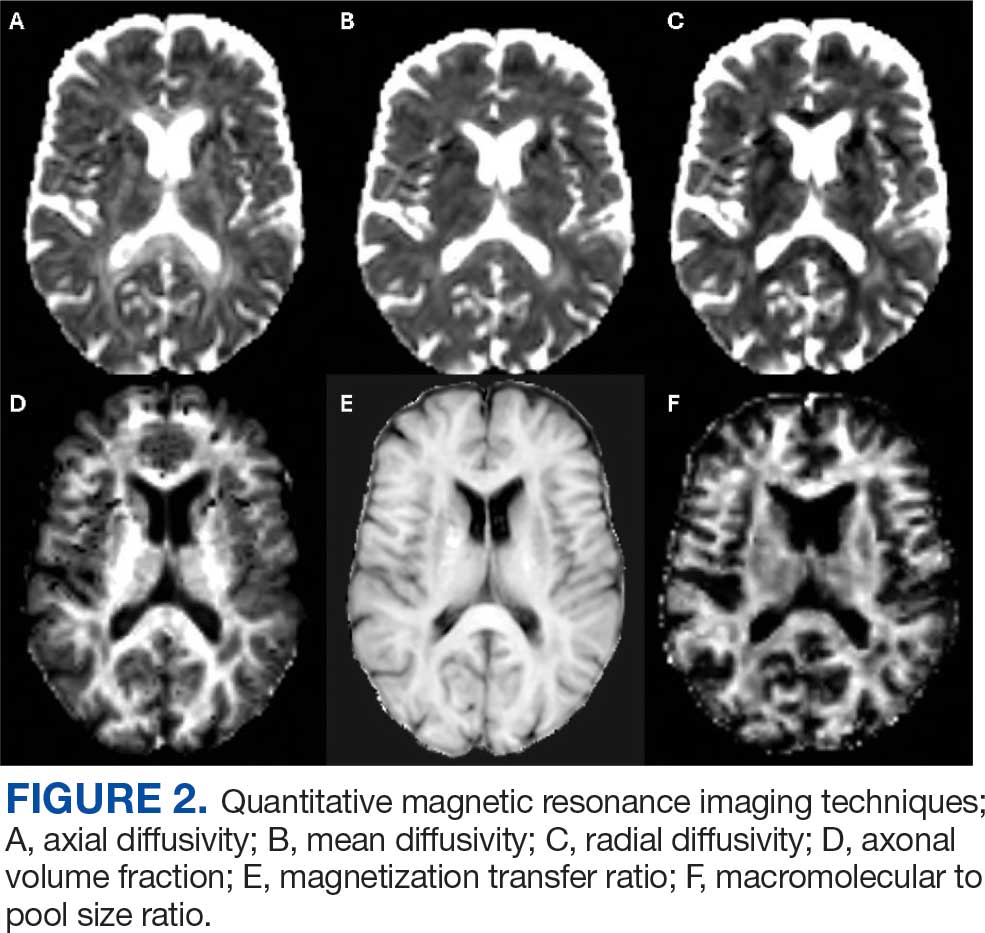

In the research setting, several imaging modalities can be used to quantify the degree of microstructural injury in PwMS. The goal of these methods is to identify and quantify myelin and axonal damage, the major drivers of neurodegeneration. Among these methods, diffusion-based imaging is a measure of the amount of diffusion or fluid mobility across the tissues of the brain.47 Diffusion-weighted imaging (DWI) yields several parametric maps including axial diffusivity (AD), radial diffusivity (RD), and mean diffusivity (Figure 2 A, B, and C). These parametric maps provide information on different directions of water molecules’ movements. Myelin surrounds the axons preventing water molecules diffusion perpendicular to axons (RD) while axonal content prevents water diffusion horizontal to the axons (AD).Thus, AD is considered more specific to axonal injury, whereas RD is specific to myelin content.48 A higher value of any of these metrics is associated with a higher degree of tissue injury.

Although sensitive to axonal and myelin injury, AD and RD computed from single b-shell DWI experience several limitations including being affected by nonpathologic factors such as fiber orientation, distribution, and crossing, and by various nonmyelin specific pathologies including fluid accumulation during inflammation, myelin sheath thickness, and axonal intactness.48 Several multi b-shell methods have been developed to overcome diffusion imaging limitations. For example, work at the Nashville VA MS Center of Excellence has focused on the use of the multicompartment diffusion MRI with spherical mean technique (SMT). This method removes the orientation dependency of the diffusion MRI signal, increasing the signal-to-noise ratio and reducing biases from fiber undulation, crossing, and dispersion.49 SMT generates the apparent axonal volume fraction (Vax), which is a direct measure of axonal integrity with lower values indicating lower axonal content and higher tissue destruction (Figure 2D). Vax was previously validated in MS as a measure of axonal integrity.49

In terms of myelin, several other specific measures have been developed. Magnetization transfer ratio (MTR) is another measure of tissue integrity that has been validated as a measure of tissue injury in MS (Figure 2E).50,51 Zheng et al found that the percentage of lesions with low MTR was significantly higher among patients whose disease disability progressed compared with patients who did not.52Selective inversion recovery with quantitative magnetization transfer (SIR-qMT) was developed to account for the limitations of MTR, including its sensitivity to edema and axonal density.52 Germane to myelin measurements, SIR-qMT generates the macromolecular to free size ratio (PSR). PSR represents the ratio of protons bound to macromolecules (myelin) to free protons (Figure 2F). PSR is considered a marker of myelin integrity, with lower values correlating with disability severity and indicating higher tissue damage and lower myelin content. Previous studies from the Nashville VA MS Center of Excellence validated the use of SIR-qMT among patients with MS, CIS, RIS, and healthy controls.53